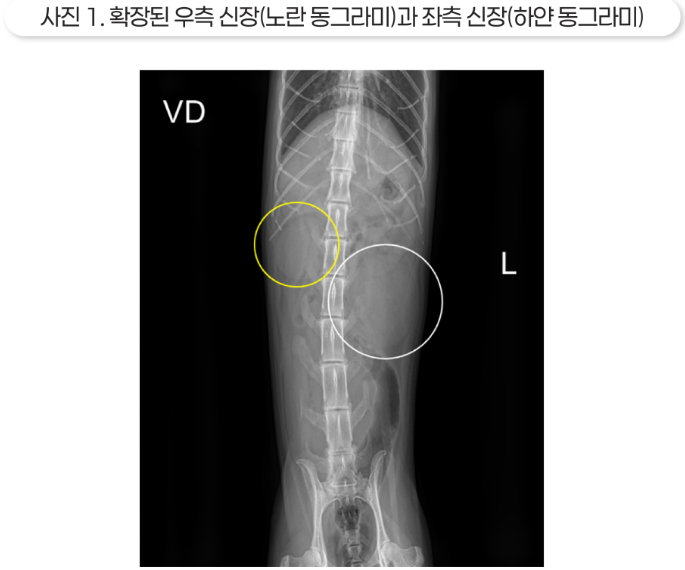

방사선 영상에서는 복수로 인해 복강 장기 전체가 보이진 않았지만 양측 신장이 모두 크게 나타났고, 특히 좌측 신장이 더 크게 나타났습니다.

초음파 영상에서는 양측 수신증과 요관 결석이 확인되었습니다.

결석보다 가까운 쪽의 요관은 확장되어 있는데, 이는 요관 폐색을 의미합니다. 신우가 매우 확장되어 있었고, 특히 오른쪽 신장은 피질이 많이 얇아져 있고 심한 수신증 소견을 보였습니다.

수신증이 너무 심하면 해당 신장은 이미 기능을 상실했을 가능성이 높습니다.